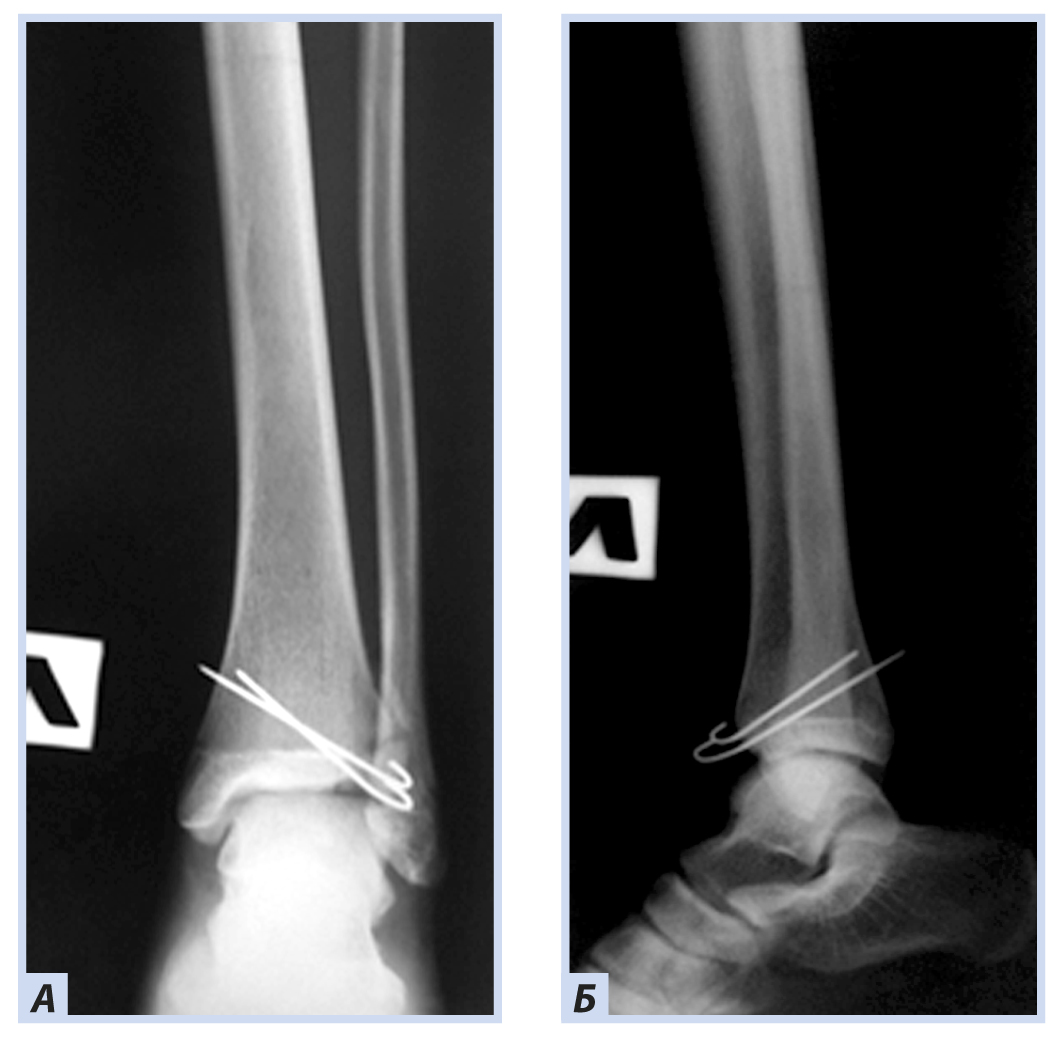

Девочка, 13 лет, диагноз: «Закрытый дистальный остеоэпифизеолиз левой большеберцовой кости, Salter–Harris III тип, Tillaux fractures». Травму получила, упав со скейтборда. По механизму травмы — супинационно-эверсионный перелом. Учитывая внутрисуставной характер перелома, остеосинтез выполнен с открытой репозицией и фиксацией отломков перекрещивающимися спицами. Дополнительная иммобилизация осуществлялась в задней гипсовой лонгете до коленного сустава. Контрольные рентгенограммы выполняли через 6 и 8 нед. после репозиции. Спицы удалены через 8 нед., конфигурация сустава восстановлена полностью (рис. 6–9).

Рис. 6. Девочка, 13 лет. Рентгенограммы дистального отдела костей левой голени. Остеоэпифизелиз дистального отдела левой большеберцовой кости Salter–Harris, III тип, Tillaux fractures: А — прямая проекция; Б — боковая проекция.

Рис. 7. Тот же пациент. Рентгенограммы дистального отдела костей левой голени. Остеосинтез перекрещивающимися спицами: А — прямая проекция; Б — боковая проекция.

Рис. 8. Тот же пациент. Рентгенограммы дистального отдела костей левой голени через 6 нед. Консолидация костных отломков: А — прямая проекция; Б — боковая проекция.